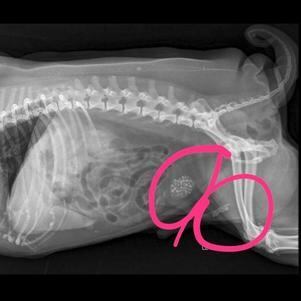

Zeus e suas pedras